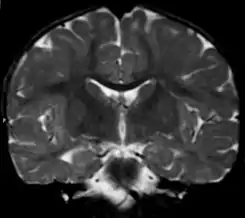

![]() Imagen de una leucodistrofia en una niña de 18 meses. Posible Enfermedad de Alexander | ||